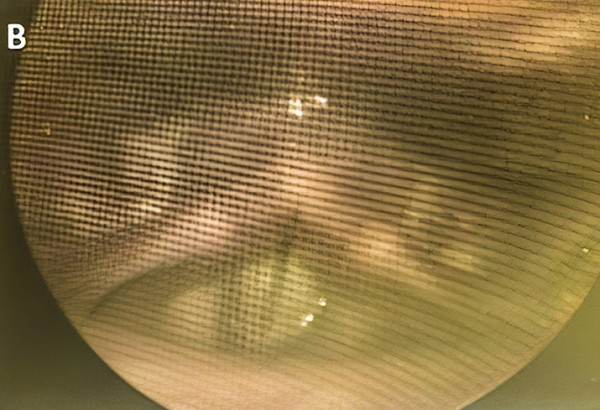

После лечения при ларингоскопическом исследовании визуализировалось полное смыкание голосовых складок у всех пациентов с недостаточностью голосового аппарата, а также имело место уменьшение передне-заднего и/или латерального сдавления вестибулярного отдела гортани (см. рис. 1).

Рисунок 1. Пациент с недостаточностью голосового аппарата до (А) и через 1 месяц после лечения (В).